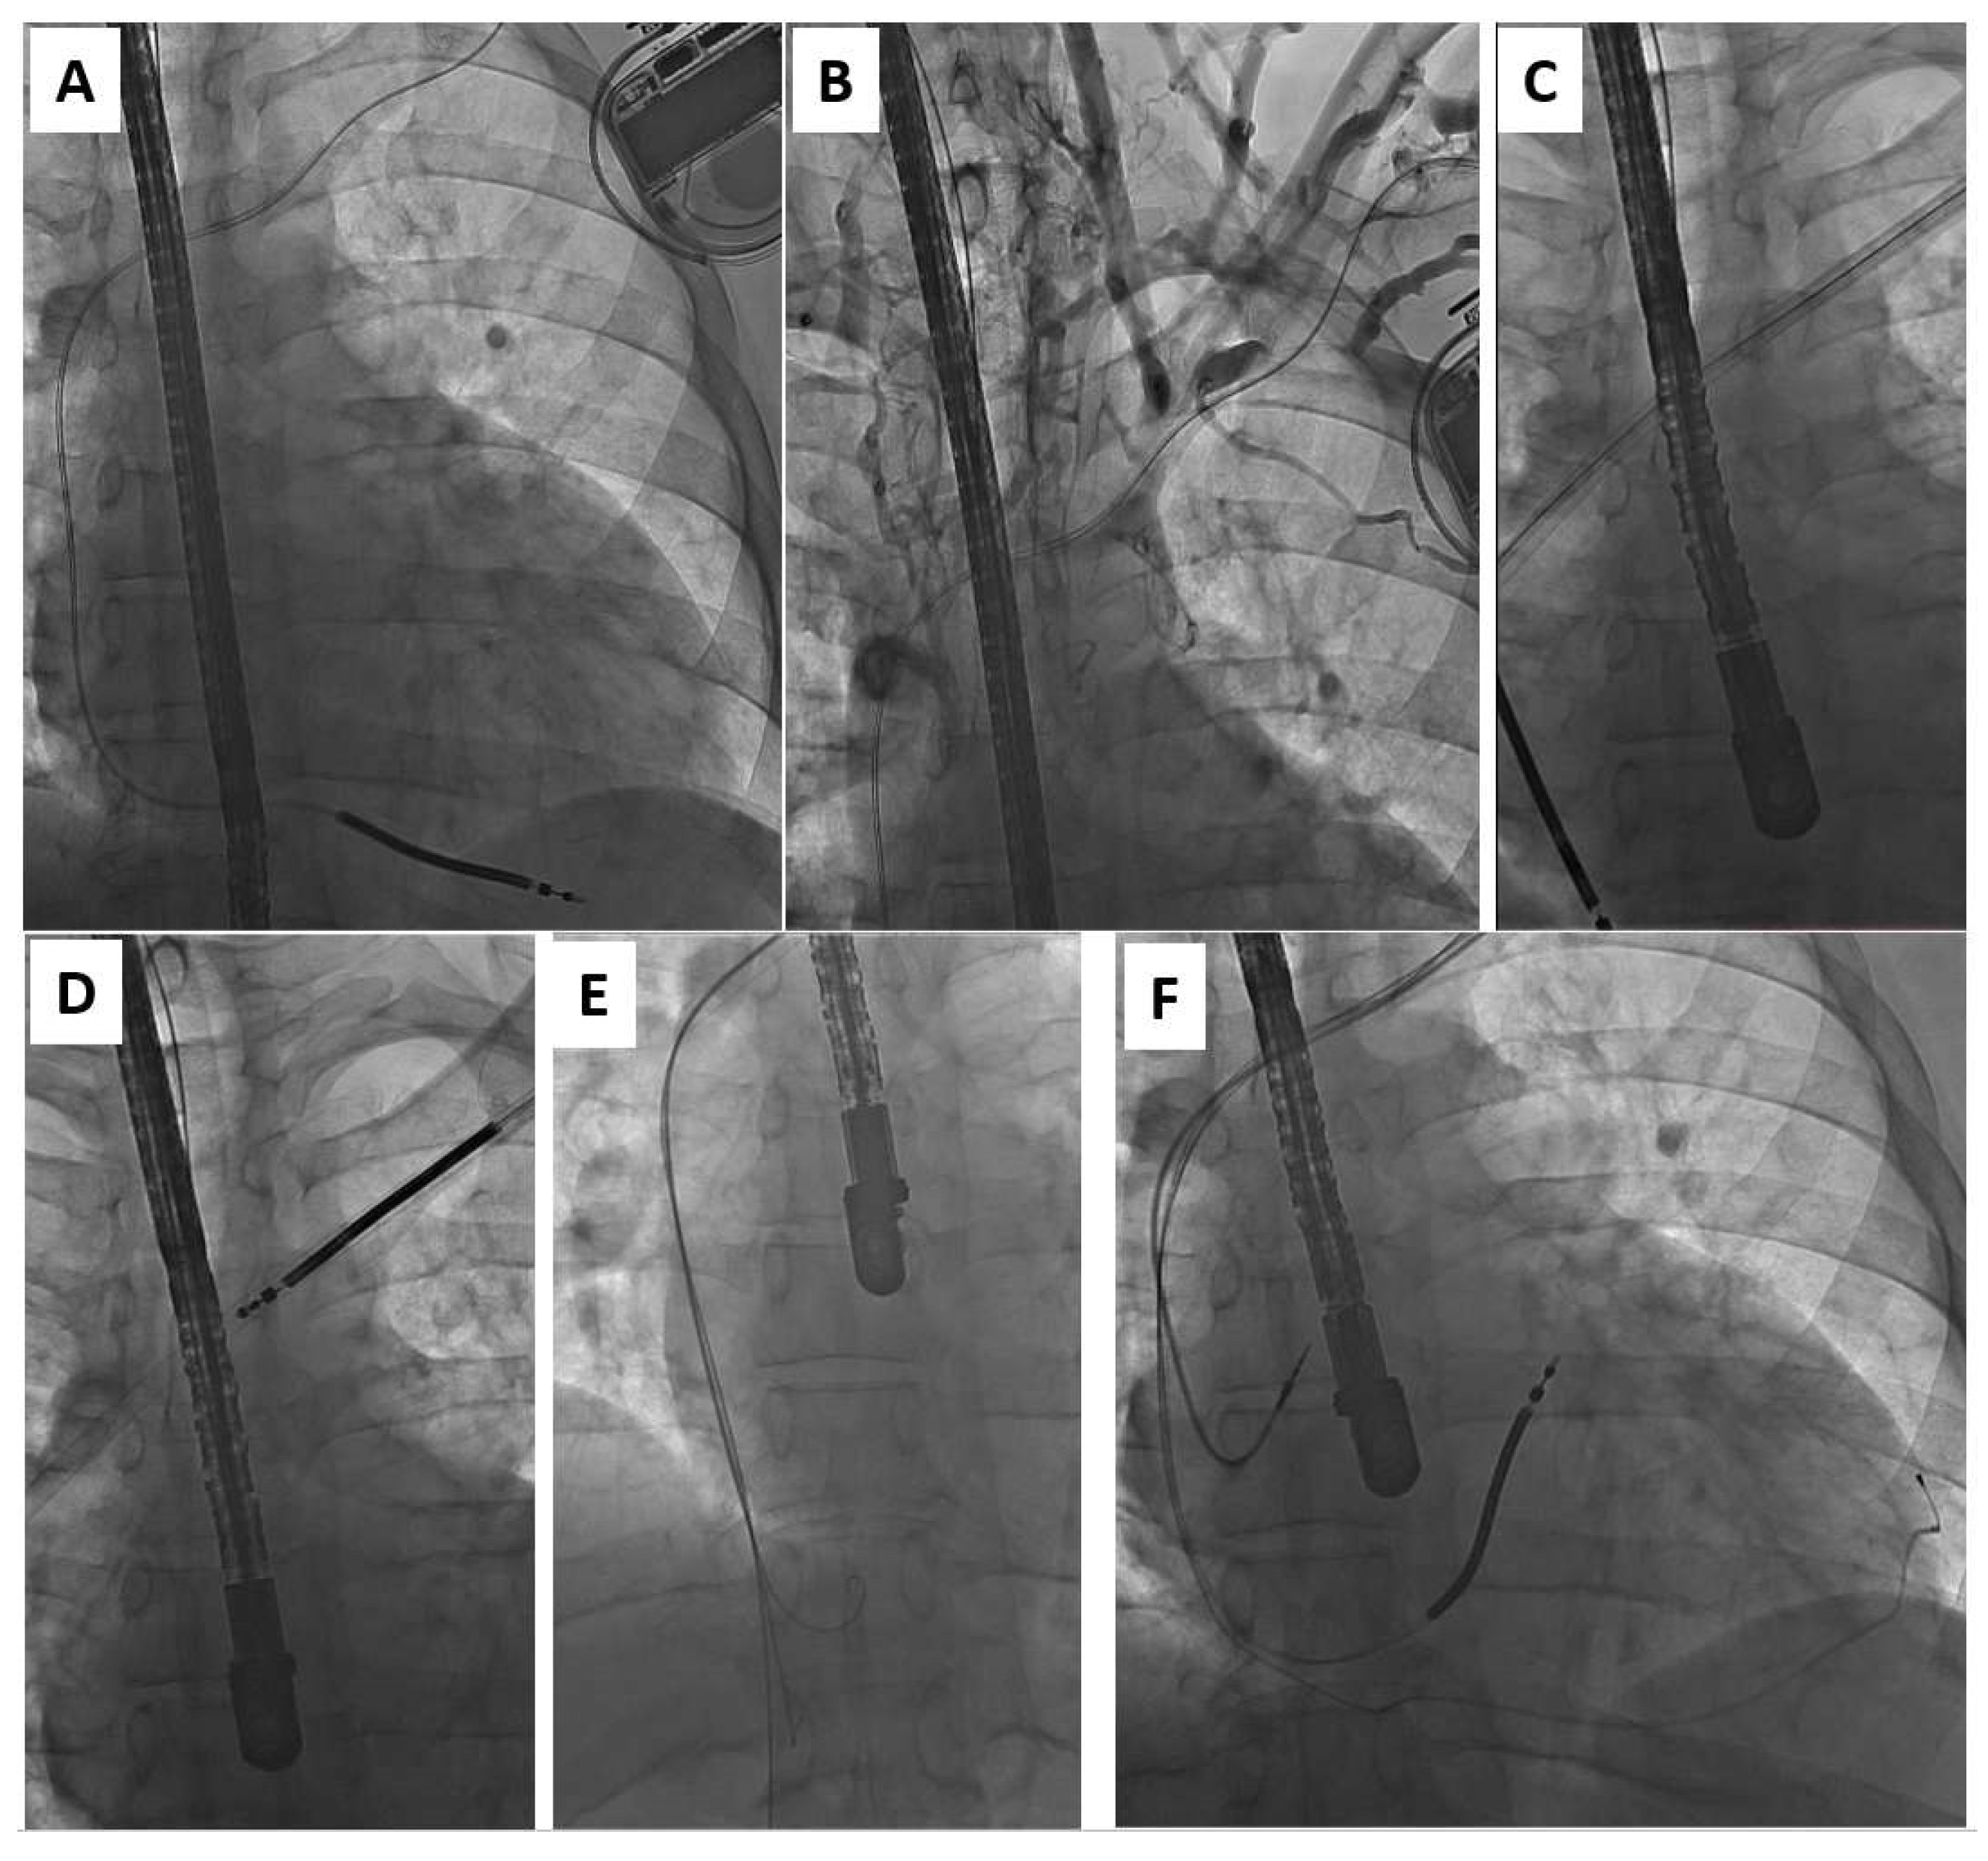

One of the most important issues in patients undergoing system upgrades is venous patency and the need to have enough space for two large introducers, which may necessitate the extraction of the existing lead. Imaging with venography is mandatory before any attempt at a system upgrade [13,14,15]. In this study, like previous reports [9,13,14,15], significant lead-related venous obstruction was found in about 60% of upgrade patients (Figure 3). Despite difficult venous access in these patients, there was no case in which a contralateral implant was necessary.

Figure 3.

Upgrade from ICD-V (A) to CRT-D in the patient with lead-related venous obstruction (B). Moving the preparation sheath over the lead to the heart allows not only for lead removal (C,D) but also reestablishing venous access (E) for the implantation of three new leads (F).